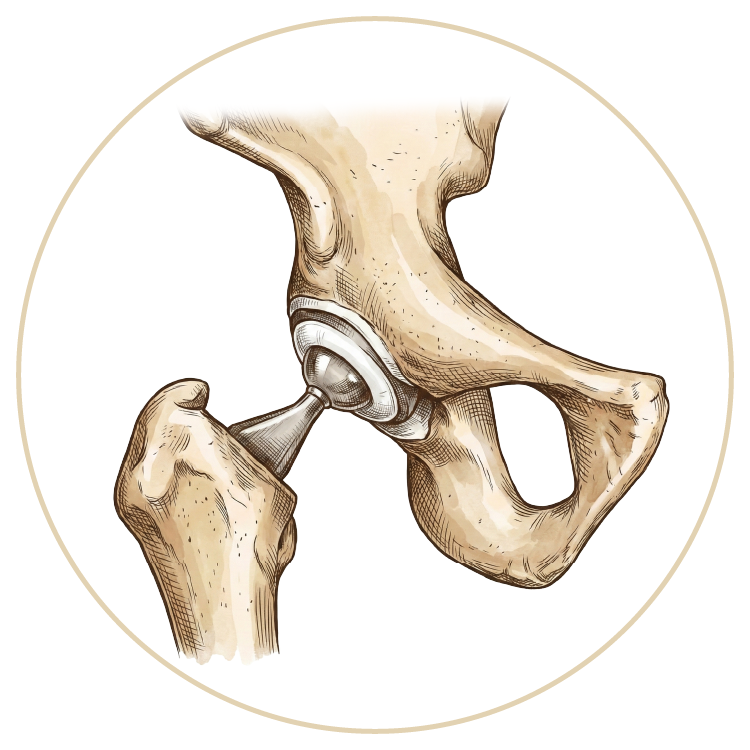

Kalça Protezi

Robotik Kalça Protezi